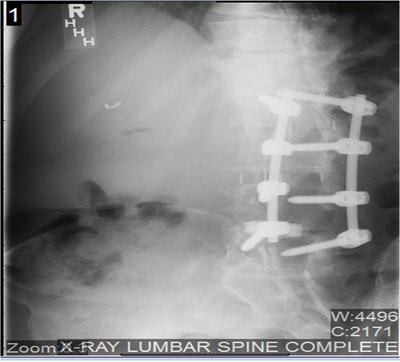

Doctor, I have a long history of back injury and issues, all beginning with a car accident in 1993. Severe adult scoliosis developed in the years following the accident. I tried everything from chiropractic, to acupuncture, to steroid injections. I had positive results from one chiropractic doctor, but, unfortunately, had to move to another location and found no one else as good. Eventually, I developed stenosis and had a great deal of pain, trouble walking, etc. I optioned for an L2-L5 fusion in 2010 - short term results were good, but only lasted a few months. The x-rays and radiology report will tell you a lot. The last doctor I saw said the pain in my left buttock was a referred pain from my spine.

2. Do you get any groin pain? The pelvic Xray doesn't have a R/L so I'm not sure which side, but one hip joint appears to have a pincer deformity. Femoro Acetabular Impingement Syndrome. That would certainly affect your walking, and if on the side of your buttock pain, could certainly be a part of the problem.

4. Yes, the T12-L1 area can refer via the Superior Cluneal nerves to the buttock. And that area doesn't look great, so it needs to be considered.